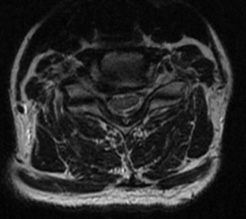

This patient is a 58 year-old female radiology technician with chronic, intractable neck pain, right > left arm radicular pain, and progressive weakness. At one point her symptoms worsened so acutely, she presented to the emergency department for acute triage with cervical CT angiogram, which showed advanced spondylosis at the C6/7 level.

The combination of the chronic problem with acute worsening of symptoms required decompression and stabilization at C6/7. Typically, at this patient age, with this advanced level of spondylosis at the C6/7 level, I would proceed with an instrumented fusion. However, this patient was very active and wanted to optimize her quality of life as possible with this surgery.

Patient is a healthy, active 58 year-old female, though with advanced degenerative spondylosis at a low cervical level. The patient had favorable anatomy with a long neck and low shoulders to facilitate intraoperative visualization. Fusion was appropriate in this case, but intraoperatively, though we were prepared for this possiblity, the disk space was well-preserved and mobilized without major modification of the endplates. The postoperative flexion and extension radiographs showed movement at the spinous processes of C6/7 and good function of the prodisc C Vivo prosthesis. The adjacent C5/6 level also shows degenerative spondylosis. By optimizing the mobility of the C6/7 level I anticipate the patient will have an improved trajectory for her cervical spine function throughout her life.